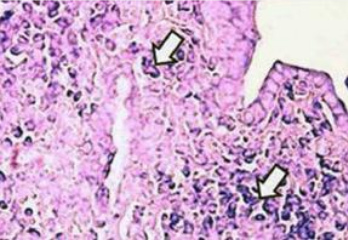

Microfotografía de pulmón de rata intoxicada por

antracenonas de una planta silvestre [11]

La acumulación de toxinas entre el capilar y las

células determinará:

Los radicales ácidos libres en el espacio

intersticial forman una barrera y destruyen los

nutrientes. Así bloquean el oxígeno y no llega

oxígeno más a las células.